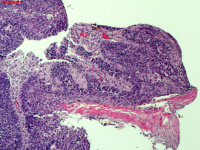

性别

男

年龄

40岁

临床诊断

肺癌?

一般病史

增强CT提示右肺中叶粘液栓;气管镜见右肺中叶外侧段新生物,考虑恶性可能。

图2

鳞状细胞癌